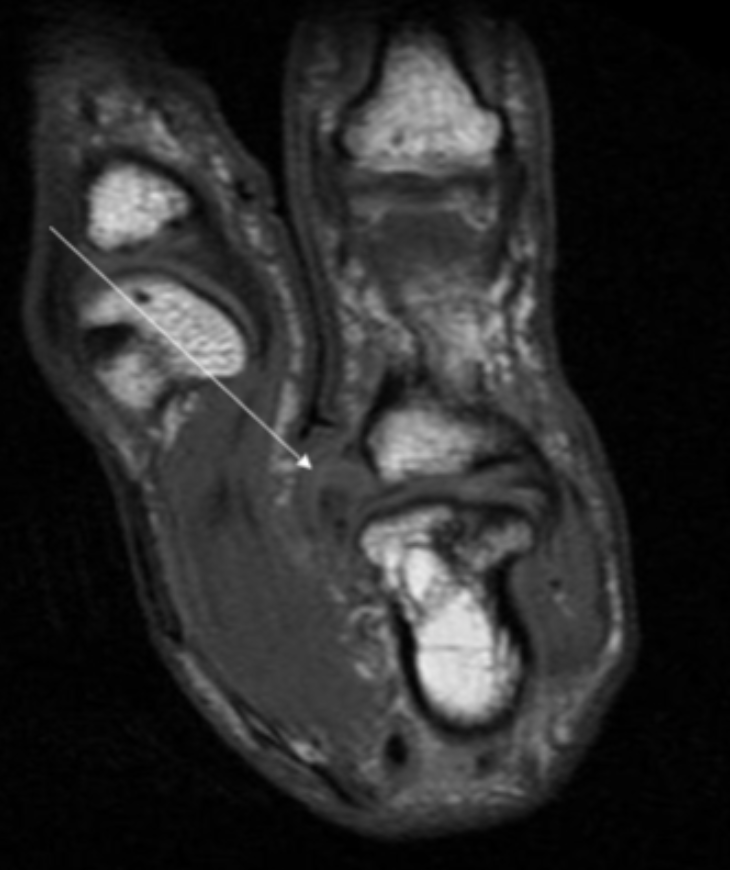

Describe the pathology indicated by the arrow (Sag PD).

Flexor tendon tear

Describe the pathology indicated by the arrow (Sag PD).

Extensor tendon tear

Describe the pathology indicated by the arrow (Sag PD).

UCL tear (Skier’s thumb)

Describe the pathology (Ax T2 FS).

Tenosynovitis